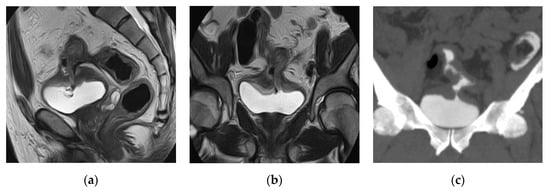

2.12. Cystitis

2.13. Eosinophilic Cystitis

| Acute infectious cystitis | Diffuse bladder wall thickening, especially if oedematous at T2 weighted image, urothelial hyperenhancement, perivesical fat stranding. |

| Mural bladder abscess | Intramural/exophytic non-enhancing fluid collection, irregular wall, often thick peripheral enhancement, usually affecting the upper bladder aspect. |